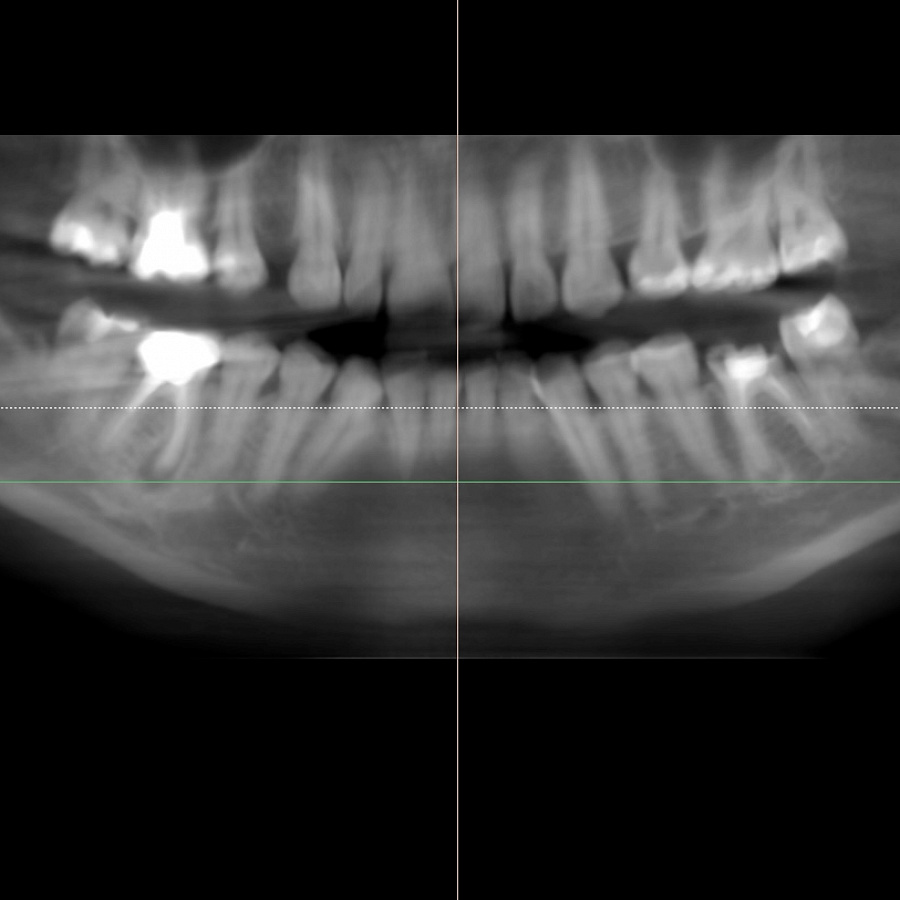

В ходе диагностики мы выяснили, что нижние шестерки вылечить невозможно. В таком случае необходимо удалить зубы и установить имплантаты.

Пациентка начала ортодонтическое лечение и за 5 месяцев до окончания лечения ей удалили нижние шестерки и поставили импланты. За месяц до конца лечения установили формирователи десны. На момент снятия брекетов были сняты слепки под постоянные коронки на имплантатах.